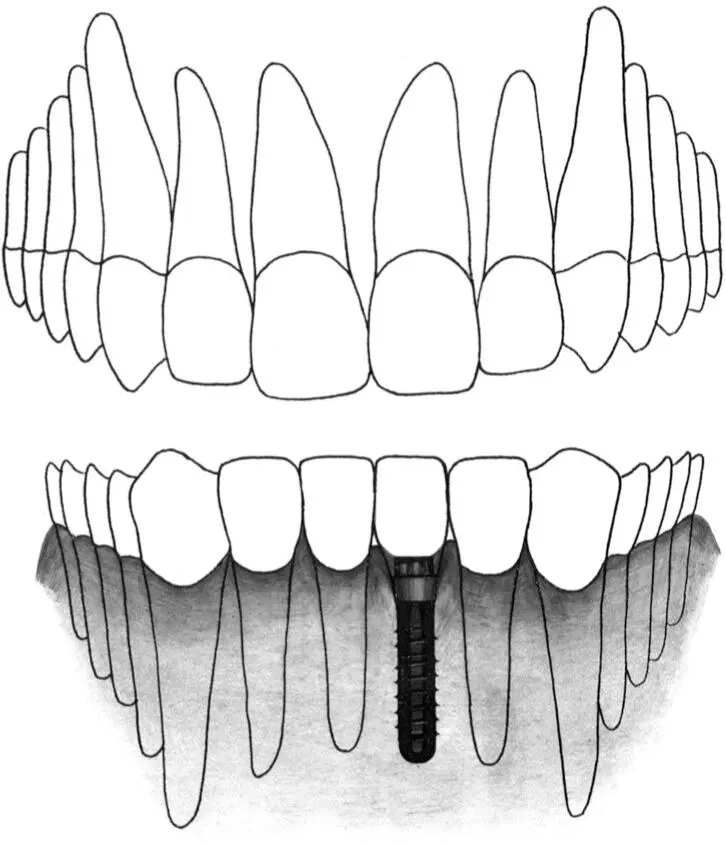

Fig 2-2 Standard plus implant.

Fig 2-2a In an esthetic restoration involving a single-tooth gap in the anterior region, a standard plus implant is indicated to replace a missing central incisor.

Fig 2-2b A standard plus implant can also be used to replace a maxillary canine in the esthetic zone.